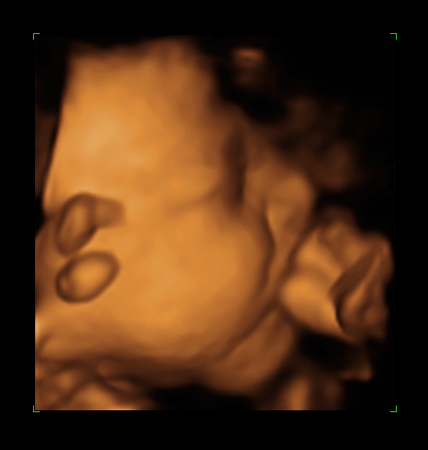

Наконец мы сделали это!!!Сегодня ходили на УЗИ.Малыш умничка, перевернулся головкой вниз)))А ещё был(а) безумно серьёзен и временами немного недоволен))))И мы сделали наши первые фотографии)))Моей радости просто нет предела!!!

а ещё у нас очень пухленькие щёчки)